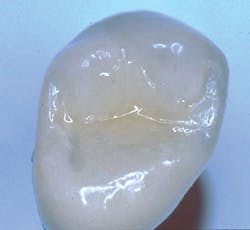

Recently, dentists and laboratory technologists have asked themselves why they were making separate abutments when many clinical situations allow use of a three-piece combination (implant, crown, and a screw through the crown into the implant) without a separate abutment. (Figs. 1-3)

FIG. 2 -- Crown on working cast. Note screw to be placed in hole through crown. Some patients object to the discoloration of the occlusal surface caused by the screw hole. Suggestions on how to restore the hole are included in this article.